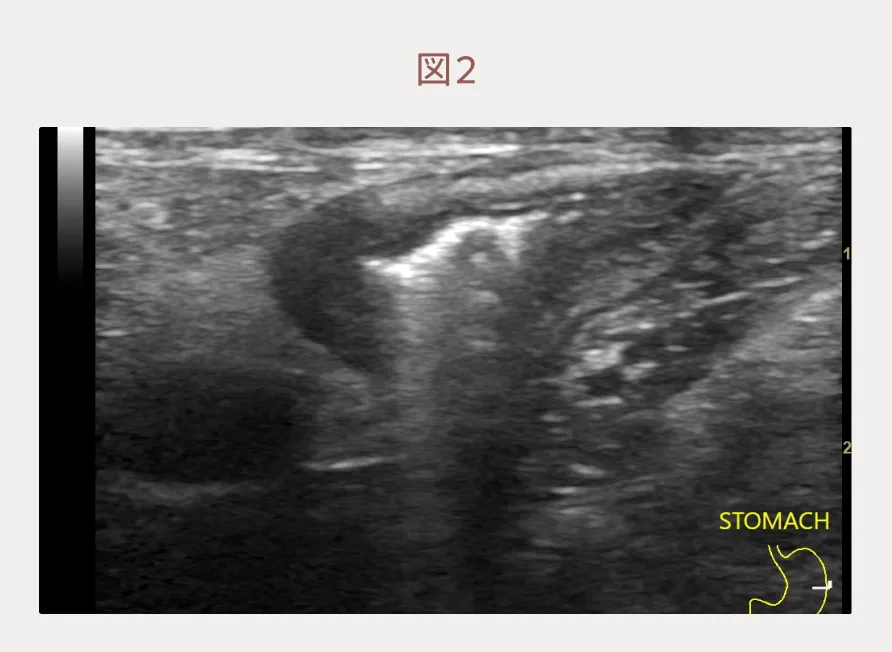

血液検査では特筆すべき異常所見はありません。しかし、エコー検査をすると胃リンパ節は腫大し(図1)、胃壁は一部で壁層構造が不明瞭で(図2)、粘膜面は不整な場所がありました。その他の腸管や内臓に画像的な異常所見はありませんでした。